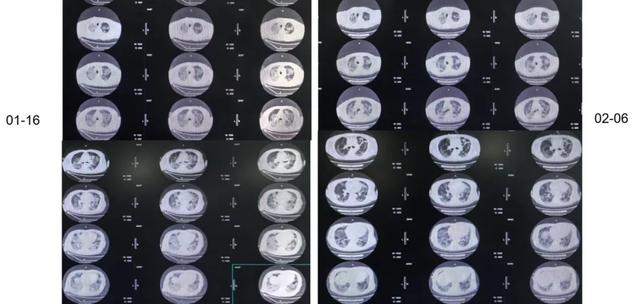

经过治疗后,1月16日我们复查胸部CT,可以看到病灶较前有所吸收。

1月26日再次复查CT,与1月16日相比,双肺下叶实变增加。

我们在2月6日复查胸部CT,发现与1月16日和1月26日相比,双肺渗出实变明显减轻。